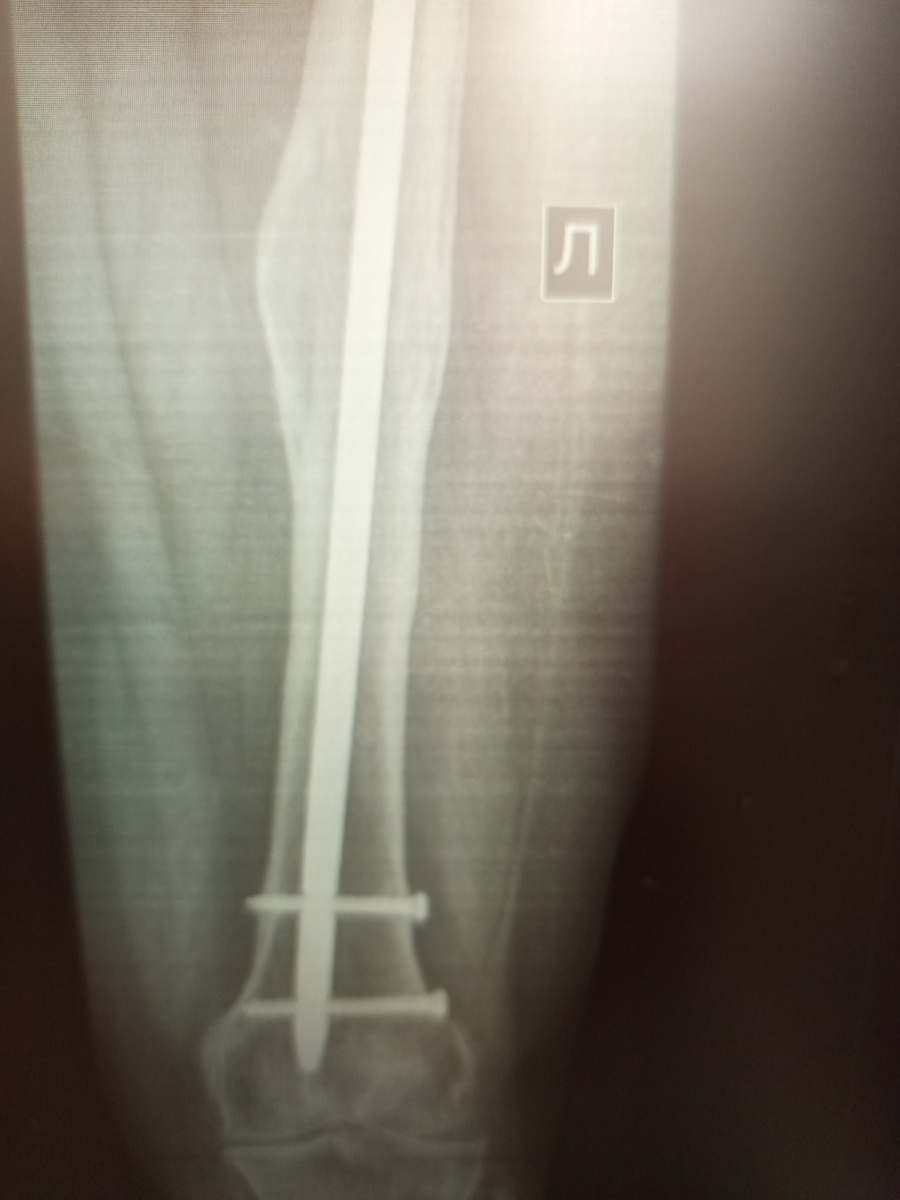

Мальчика привели, знакомый мальчик, я постоянно его снимаю то на приемнике , то на стационарном кабинете.

Год назад, будучи в нетрезвом состоянии его сбил мотоциклист. Голень сильно пострадала. У нас лежит уже четвертый раз. Ему установили аппарат Илизарова, с целью наращения кости,но , постоянно , то свищь образуется, то нагноение вокруг винтов.

В этот раз уже костная мозоль хорошо образовалась.